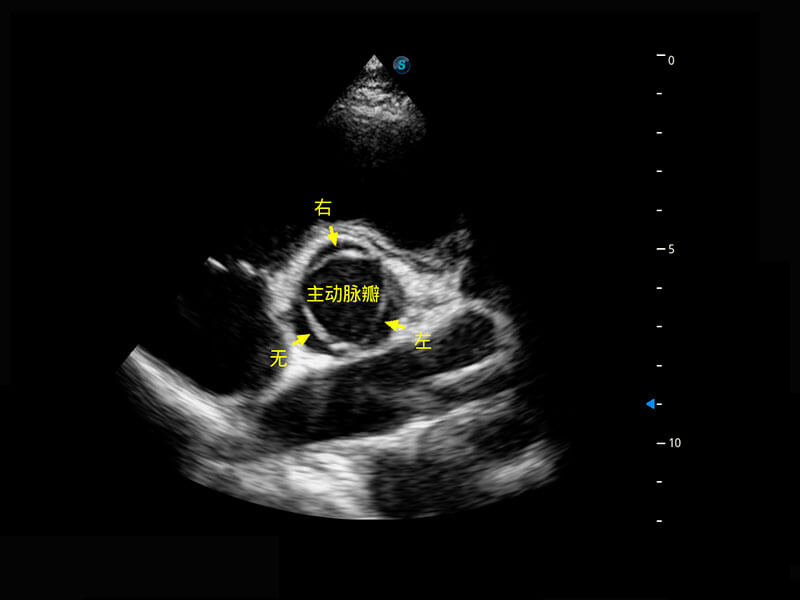

乳腺超声 / 新生儿

P60搭载宽频带线阵探头、宽景成像、弹性成像技术,为您提供乳腺应用方案。P60支持高频相控阵探头、线阵探头、腹部高频探头、腹部微凸探头等,丰富的探头群搭载敏感的彩色血流成像,适用于新生儿多种脏器检测要求,满足新生儿筛查需求。

• 新生儿肝血管癌

• 新生儿脊髓圆锥

• 新生儿心脏